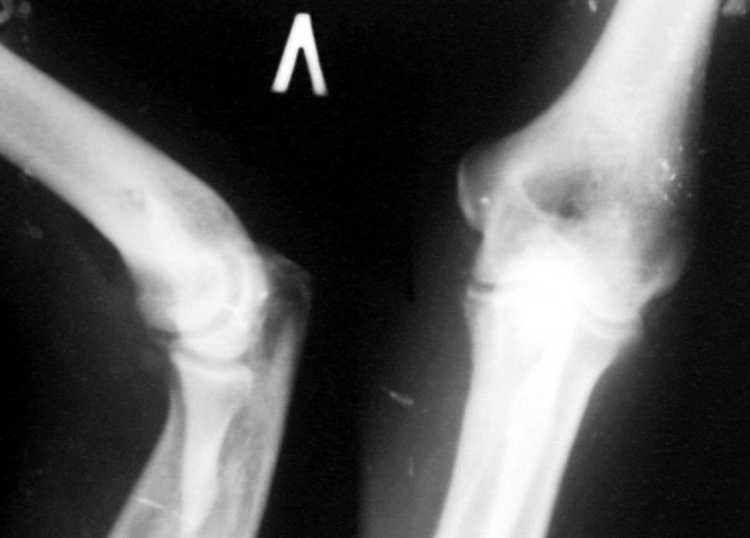

Поступил пациент, 47 лет. травма 15 сентября - вывих предплечья, репозиция. Фиксация 1 месяц. До настоящего времени не обращался. Вот рентенограммы на 2-й и 3-й месяцы после травмы. Неврологии нет. Имеется контрактура локтевого сустава (сгибиние 90, разгибание 120). На снимках что-то похожее на гетеротопические оссификаты, такое впечатление. Как лучше восстановить функцию, возможно ли применить редрессацию? Все-таки локтевой сустав "капризный".С ув. Sergey Melashenko, г. Запорожье

Dear colleguaes! I almost sure this elbow after dislocation and clouse readuction treatment.Despite pure quality of x-ray picture

I suspect small detachment fragment from coronal process.He is lucky guy that haven't instability.

In other side stiff elbow isn't happy prise in the life. In this case I would like to go to open arthrorisis(Column operation ) release anterior joint capsula and after that if you achieve range of movment good on the operation table can use physiotherapy-active assistance exersise and Univerasal elbow brace fixation. If you have not acceptable movement in the operation ( I mean in this case flexion extension 70-150 wiil be good)